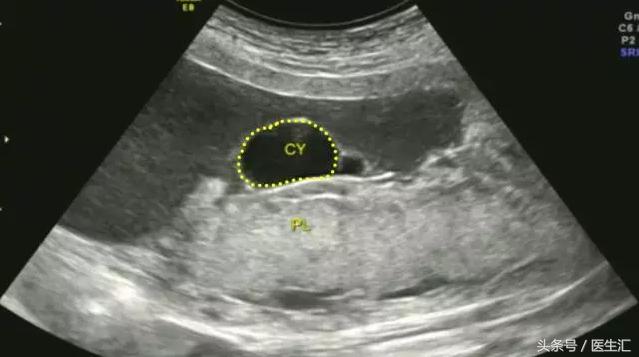

3.胎盘囊肿:位于胎盘内的羊膜面或母面,边缘清楚,圆形,内为无回声。(见图4黄色圈内)

图4,胎盘胎儿面可见一囊性包块突向羊水中,大小约30mm×15mm,边界清,内部透声好。